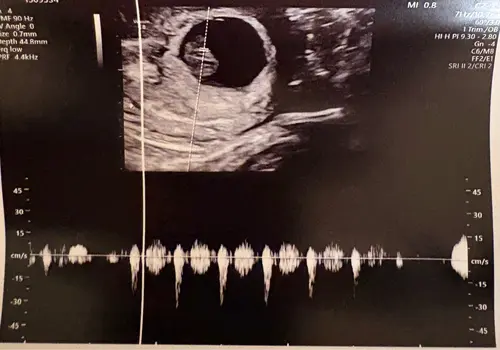

Deze beter misschien?

Ik denk een meisje, maar ik ben geen prof 馃ぃ馃ぃ